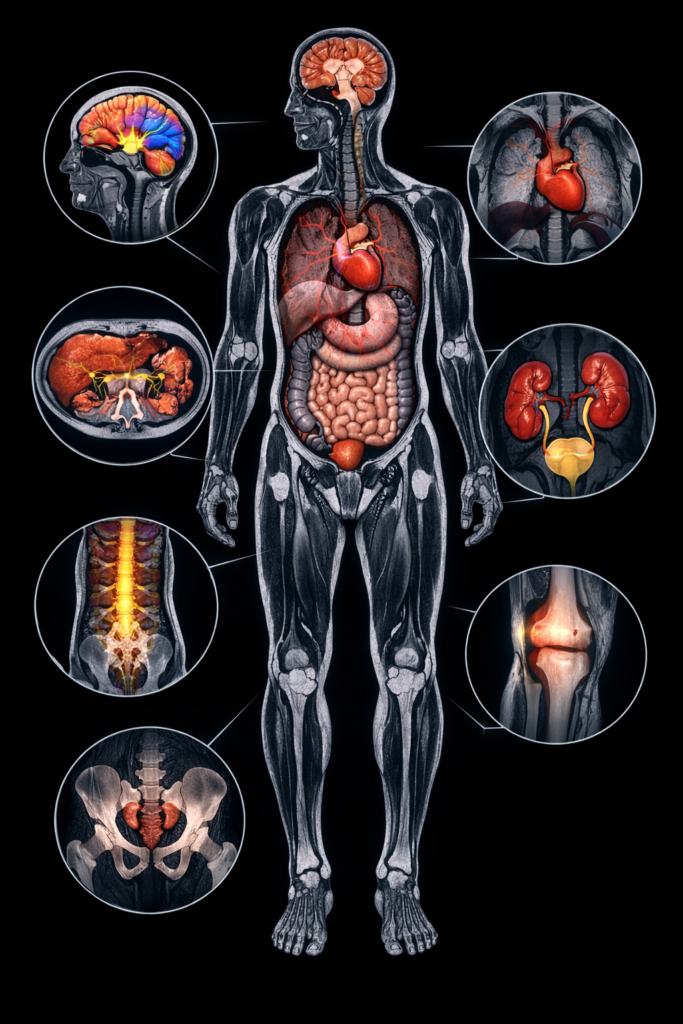

A full-body MRI scan would give the entire body a clear picture. This is also one of the most common type of MRI scan in Jaipur, which is often used for:

This scan is increasingly gaining popularity in health assessment of the entire body.

MRI scans have been utilized in the diagnosis of a broad spectrum of conditions. The brain and spine, joint, and whole body MRI are all types of MRI scan in Jaipur, which are used for a purpose.

The ability to learn the various methods of the MRI scan may make you feel more knowledgeable and courageous when taking a diagnostic test. MRI offers detailed and precise information, whether it is for treating pain, injury, or preventive care, hence aiding in making better medical choices.